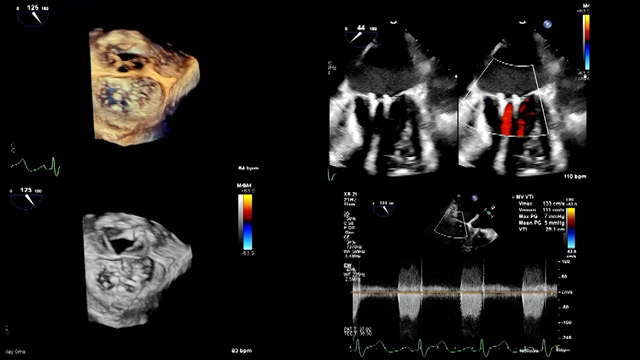

Mastering mitral TEER: guidelines, complex cases, and Asia Pacific insights

14 Feb 2026 – From PCR Tokyo Valves 2026

Focused on mastering mitral transcatheter edge-to-edge repair (TEER), this session analyzed the 2025 ESC VHD guidelines and their clinical implications. It addressed optimal timing and treatment strategies for severe heart failure beyond the COAPT trial and explored technical solutions for complex anatomies, including customization approaches for...